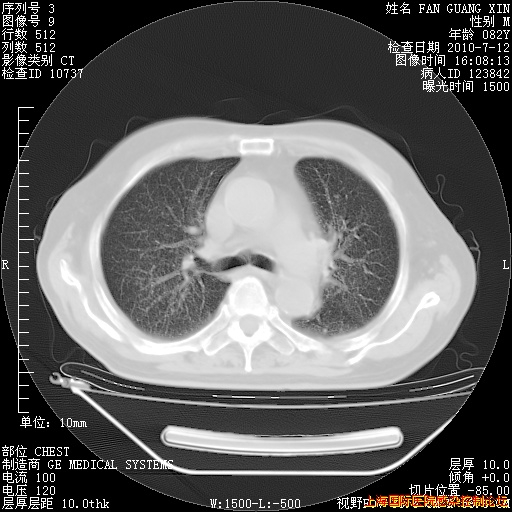

补发6月12日肺部CT肺窗

6月12日肺窗